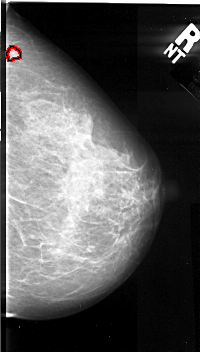

A_1061_1.RIGHT_MLO

FILE: A_1061_1.RIGHT_MLO.OVERLAY

TOTAL_ABNORMALITIES 1

ABNORMALITY 1

LESION_TYPE MASS SHAPE LOBULATED MARGINS CIRCUMSCRIBED

ASSESSMENT 3

SUBTLETY 5

PATHOLOGY MALIGNANT

TOTAL_OUTLINES 1

BOUNDARY